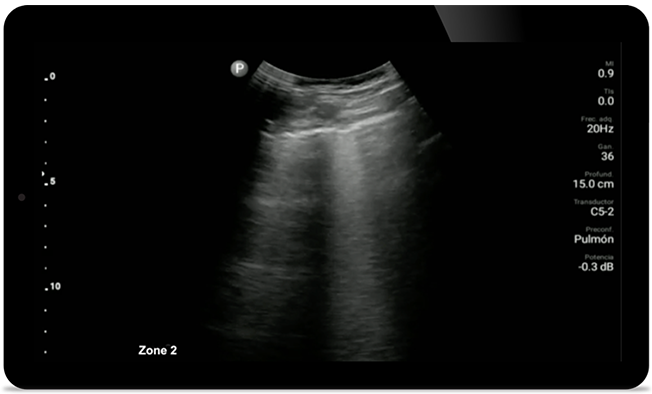

Fique de olho na pneumonia COVID

O Lumify pode ajudar a dar resultados semelhantes a uma TC de tórax ao avaliar pneumonia e síndrome do desconforto respiratório em adultos.